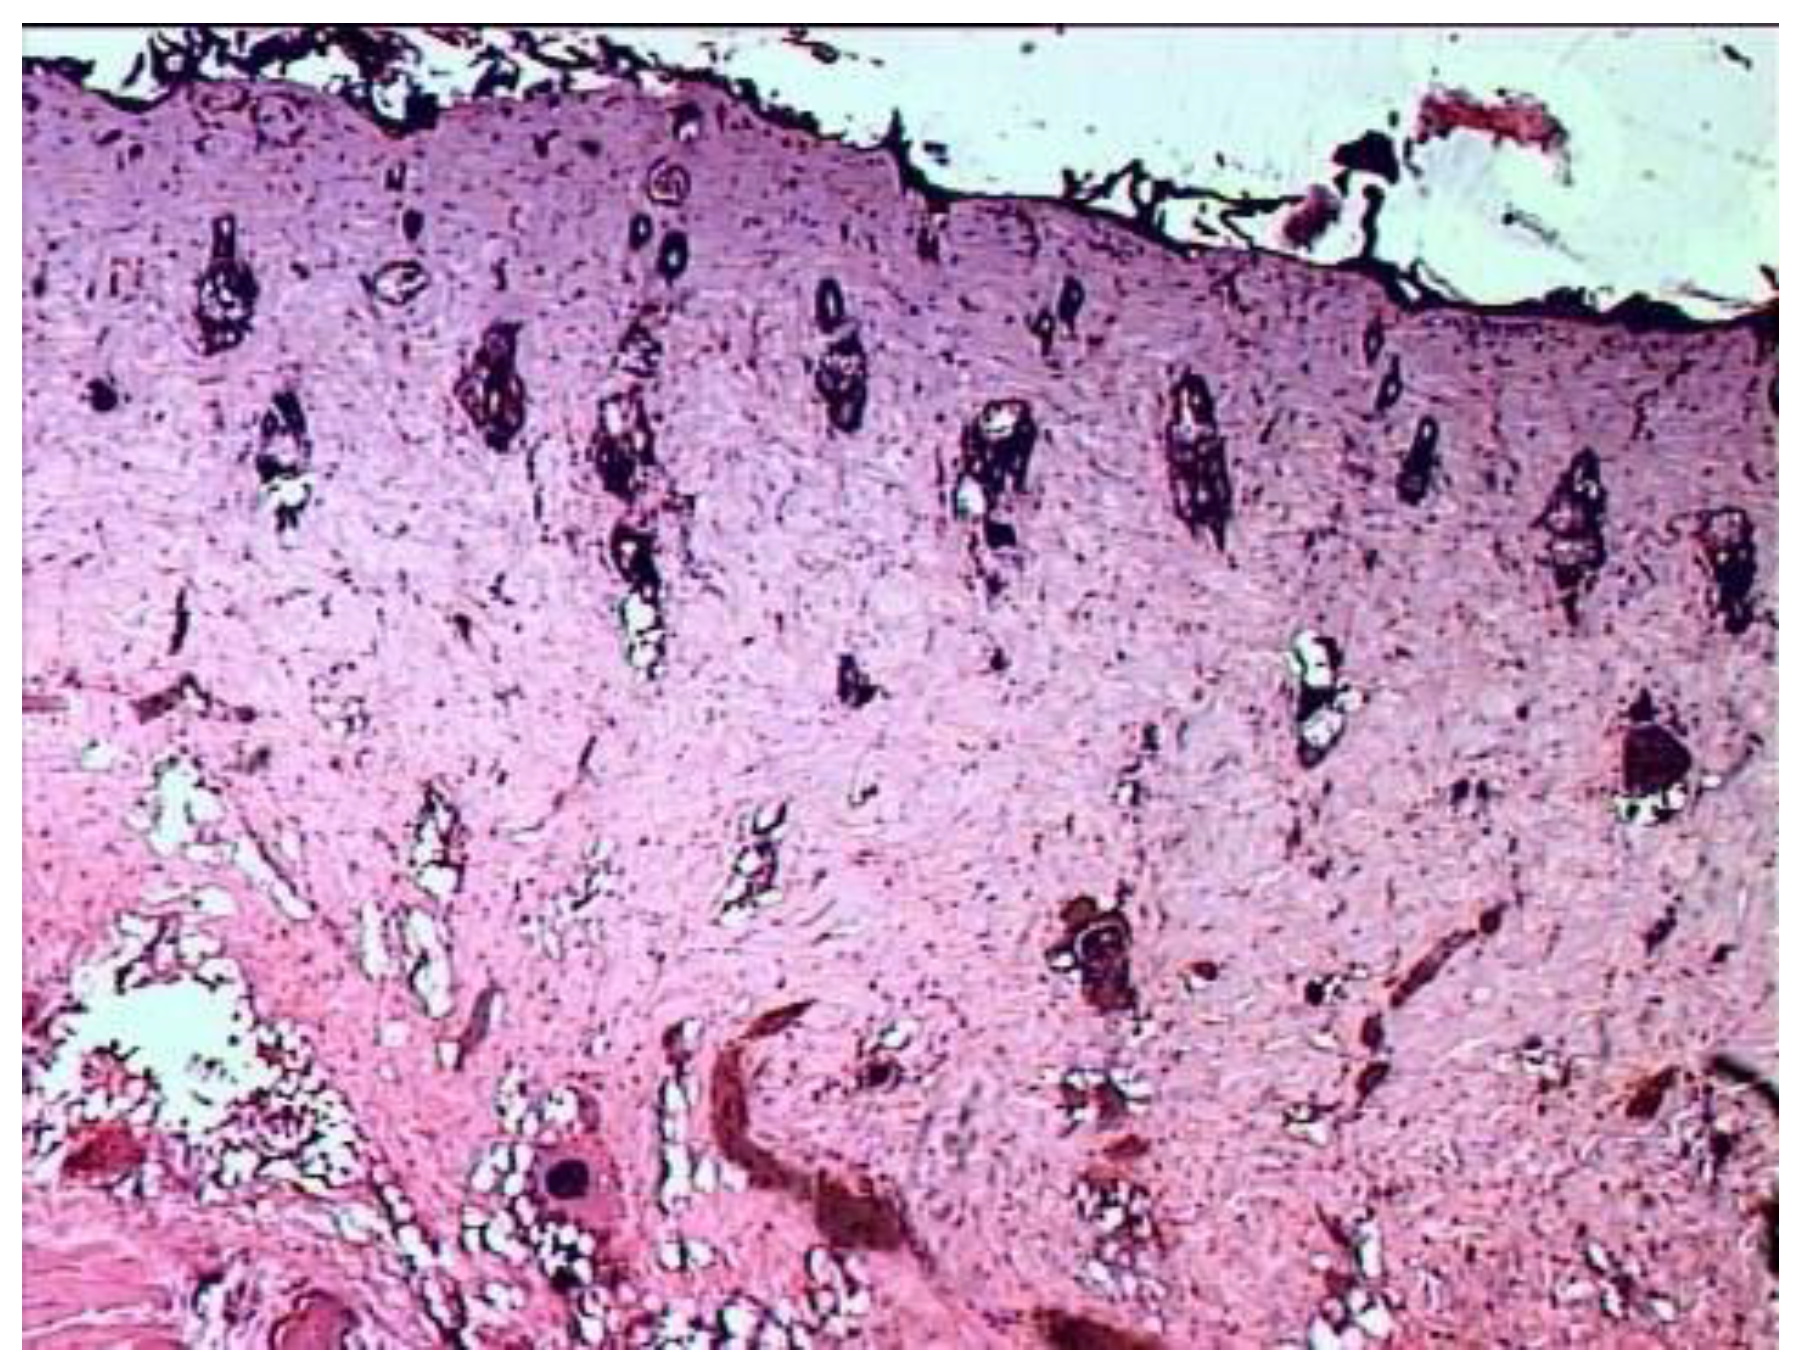

Seven days after the injury, in the group of animals whose wounds were treated with ozonated oil, purulent inflammation prevails, which is noted in the form of purulent exudate on the wound surface among the necrotic epidermis and under it, as well as in the form of focal purulent infiltrates in the necrotic dermis (Figure 3).

A continuous demarcation shaft is not formed, but, nevertheless, its placement in the dermis is indicated by leukocyte infiltrates located, albeit discretely, but at a short distance from each other. Individual leukocyte infiltrates occur at different depths of the necrotic dermis up to the skin’s own muscle. Against this background, the initial phenomena of marginal epithelialization of the skin are noted. The tongues of the epidermis proliferating from the edges of the wound are embedded under the scab, separating it from the rest of the dermis mass. Under the skin’s own muscle, there is also a pronounced proliferation of cells with large nuclei and basophilic cytoplasm. The predominant part of them has a fusiform shape (fibroblasts). There are newly formed thin-walled vessels containing red blood cells. There are single muscle buds in the muscle tissue.

Figure 3. Histological picture of the wound seven days after the application of the burn during treatment with ozonated oil. The scab is infiltrated in places by segmented leukocytes; clusters of microbial colonies are visible in it. Purulent exudate is determined under the scab. In the necrotic dermis—microabsesses. 1—scab. 2—purulent exudate. Stained with hematoxylin and eosin. magn. ×200.